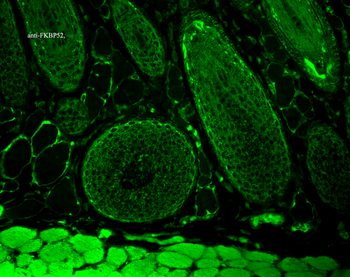

50 μl, 100 μl, 200 μlFKBP52 Antibody: APC [orb147210]

ICC, IF, IHC

Canine, Hamster, Human, Mouse, Rat

Mouse

Monoclonal

APC

100 μgFKBP52 Antibody: Biotin [orb147211]

ELISA, ICC, IF, IHC, WB

Canine, Hamster, Human, Mouse, Rat

Mouse

Monoclonal

Biotin

100 μg